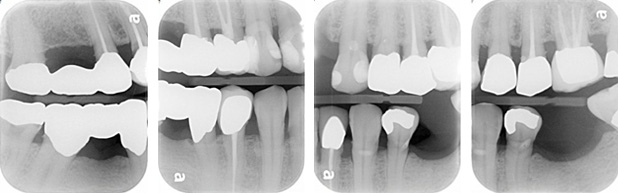

X-rays

- Interproximal calculus: 17M, 15D, 25MD, 26D, 33M, 37M, 47D, 48M

- Generalized mild horizontal bone loss

- Widening of PDL space: 35M/D

- 1:1 crown to root ratio: 26

- Apical radiolucency: 25

- Short root filling: 25